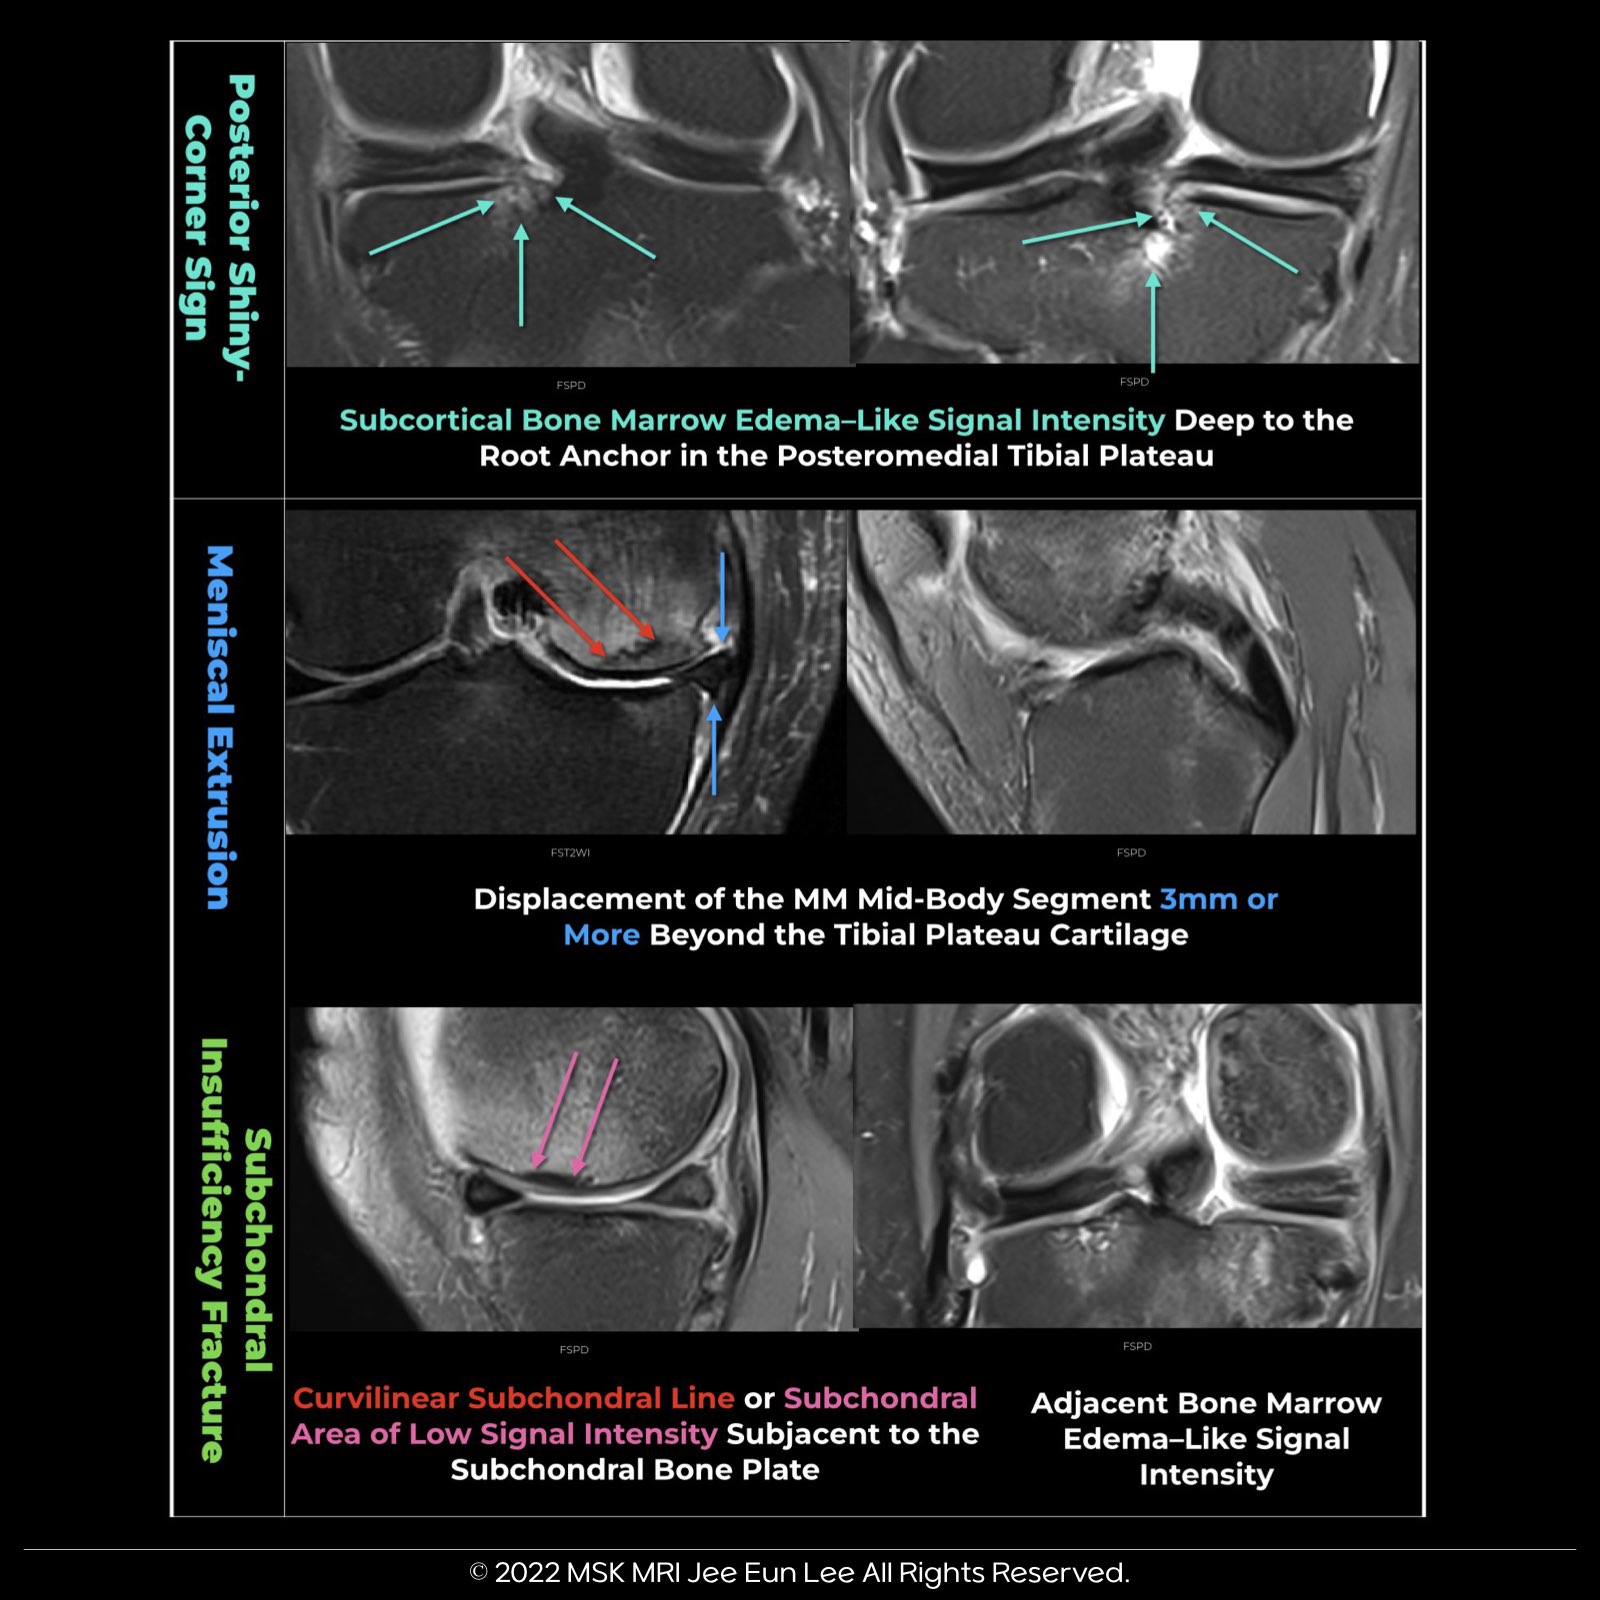

- MM extrusion refers to the displacement of the midbody segment of the medial meniscus by 3 mm or more beyond the tibial plateau cartilage, as visualized on a coronal image.

- It's significantly more likely to occur in knees with a posterior root tear, but can also be seen in cases of large radial meniscus tears, osteoarthritis, and lower extremity malalignment (e.g., knee varus).

- This sign involves subcortical bone marrow edema-like signal intensity deep to the root anchor in the posteromedial tibial plateau, with a sensitivity of approximately 62%.

- It's a useful diagnostic tool, especially when performing an early-phase MRI examination following the onset of a medial meniscus posterior root tear (MMPRT).

- These fractures typically occur at the mid-medial femoral condyle and can appear as a curvilinear subchondral infraction line or a hemispheric subchondral sclerotic focus.

- There are two key components: a) A hypointense line in the subarticular marrow, often irregular or discontinuous, parallel to the subchondral bone plate. b) An area of low signal intensity immediately below, creating a thickened subchondral bone plate appearance. This includes a combination of fracture with callus, granulation tissue, and secondary osteonecrosis between the fracture line and the articular surface.